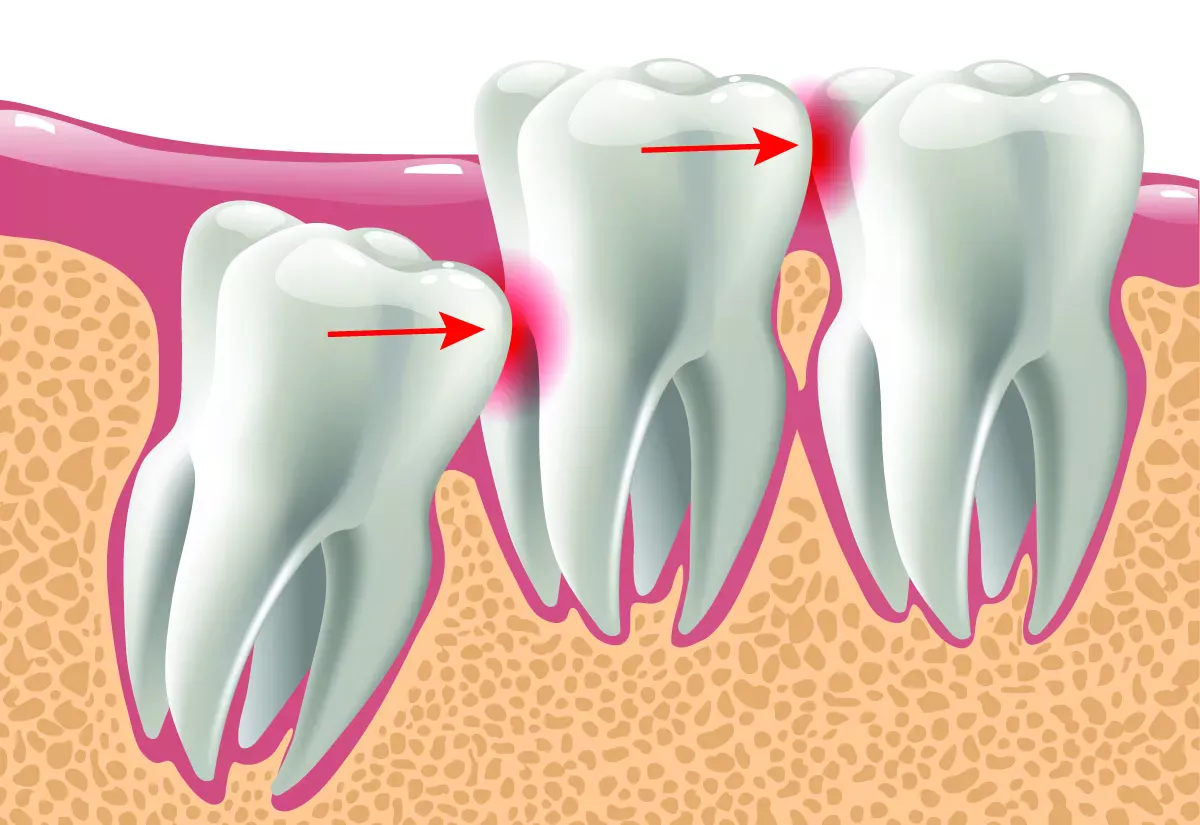

Partially retained wisdom teeth

If wisdom teeth try to break through when there is actually no room in the mouth, this can cause severe pain. The wisdom tooth then not only presses against the gum that stretches over it, but also against the neighbouring tooth. It can happen that the neighbouring molar tooth hurts terribly, even though there is no caries or root inflammation. This is referred to as a "partially retained wisdom tooth": The tooth is still partially under the gum and cannot break through. A kind of gum cap often forms over the tooth. This cap can become inflamed very easily because it is difficult to reach with a toothbrush and provides an ideal breeding ground for bacteria.

In the case of partially retained wisdom teeth, the following symptoms may occur in addition to the normal eruption symptoms:

• Severe pain

• Throbbing pain

• Earache, tinnitus

• Headaches, migraines

• Sore throat

• Neck pain

• Fever

• Tooth displacement

If you feel a throbbing pain that radiates into your ear and temples and you also have a fever, you should go to the dentist immediately.

Impacted wisdom teeth

If the wisdom teeth do not grow into the mouth at all, but remain in the jaw, they are referred to as "impacted wisdom teeth". People with impacted wisdom teeth often have no symptoms. However, if the wisdom tooth sits at an angle in the jaw and presses on a neighbouring tooth, it can damage the tooth. This can result in root caries, bone loss in the jaw or the teeth shifting due to the pressure.

Cysts can also form on impacted wisdom teeth, which the dentist can recognise on an X-ray. Cysts are filled with fluid and do not initially cause any pain. However, if they become inflamed, they can cause a feeling of pressure and dull pain.